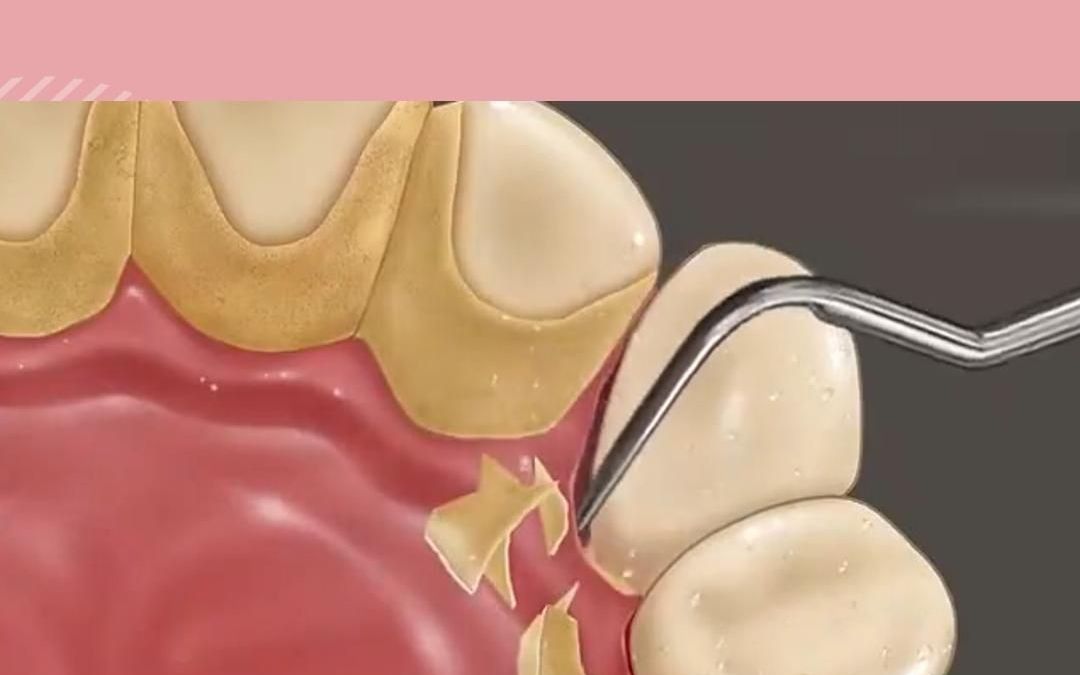

动画演示 清理牙结石过程

什么是牙结石 牙结石是指正在钙化或已经钙化的菌斑及软垢,沉积在

牙结石如何一步步"攻占"牙齿 牙结石由牙菌斑钙化沉积形成,是口腔健康